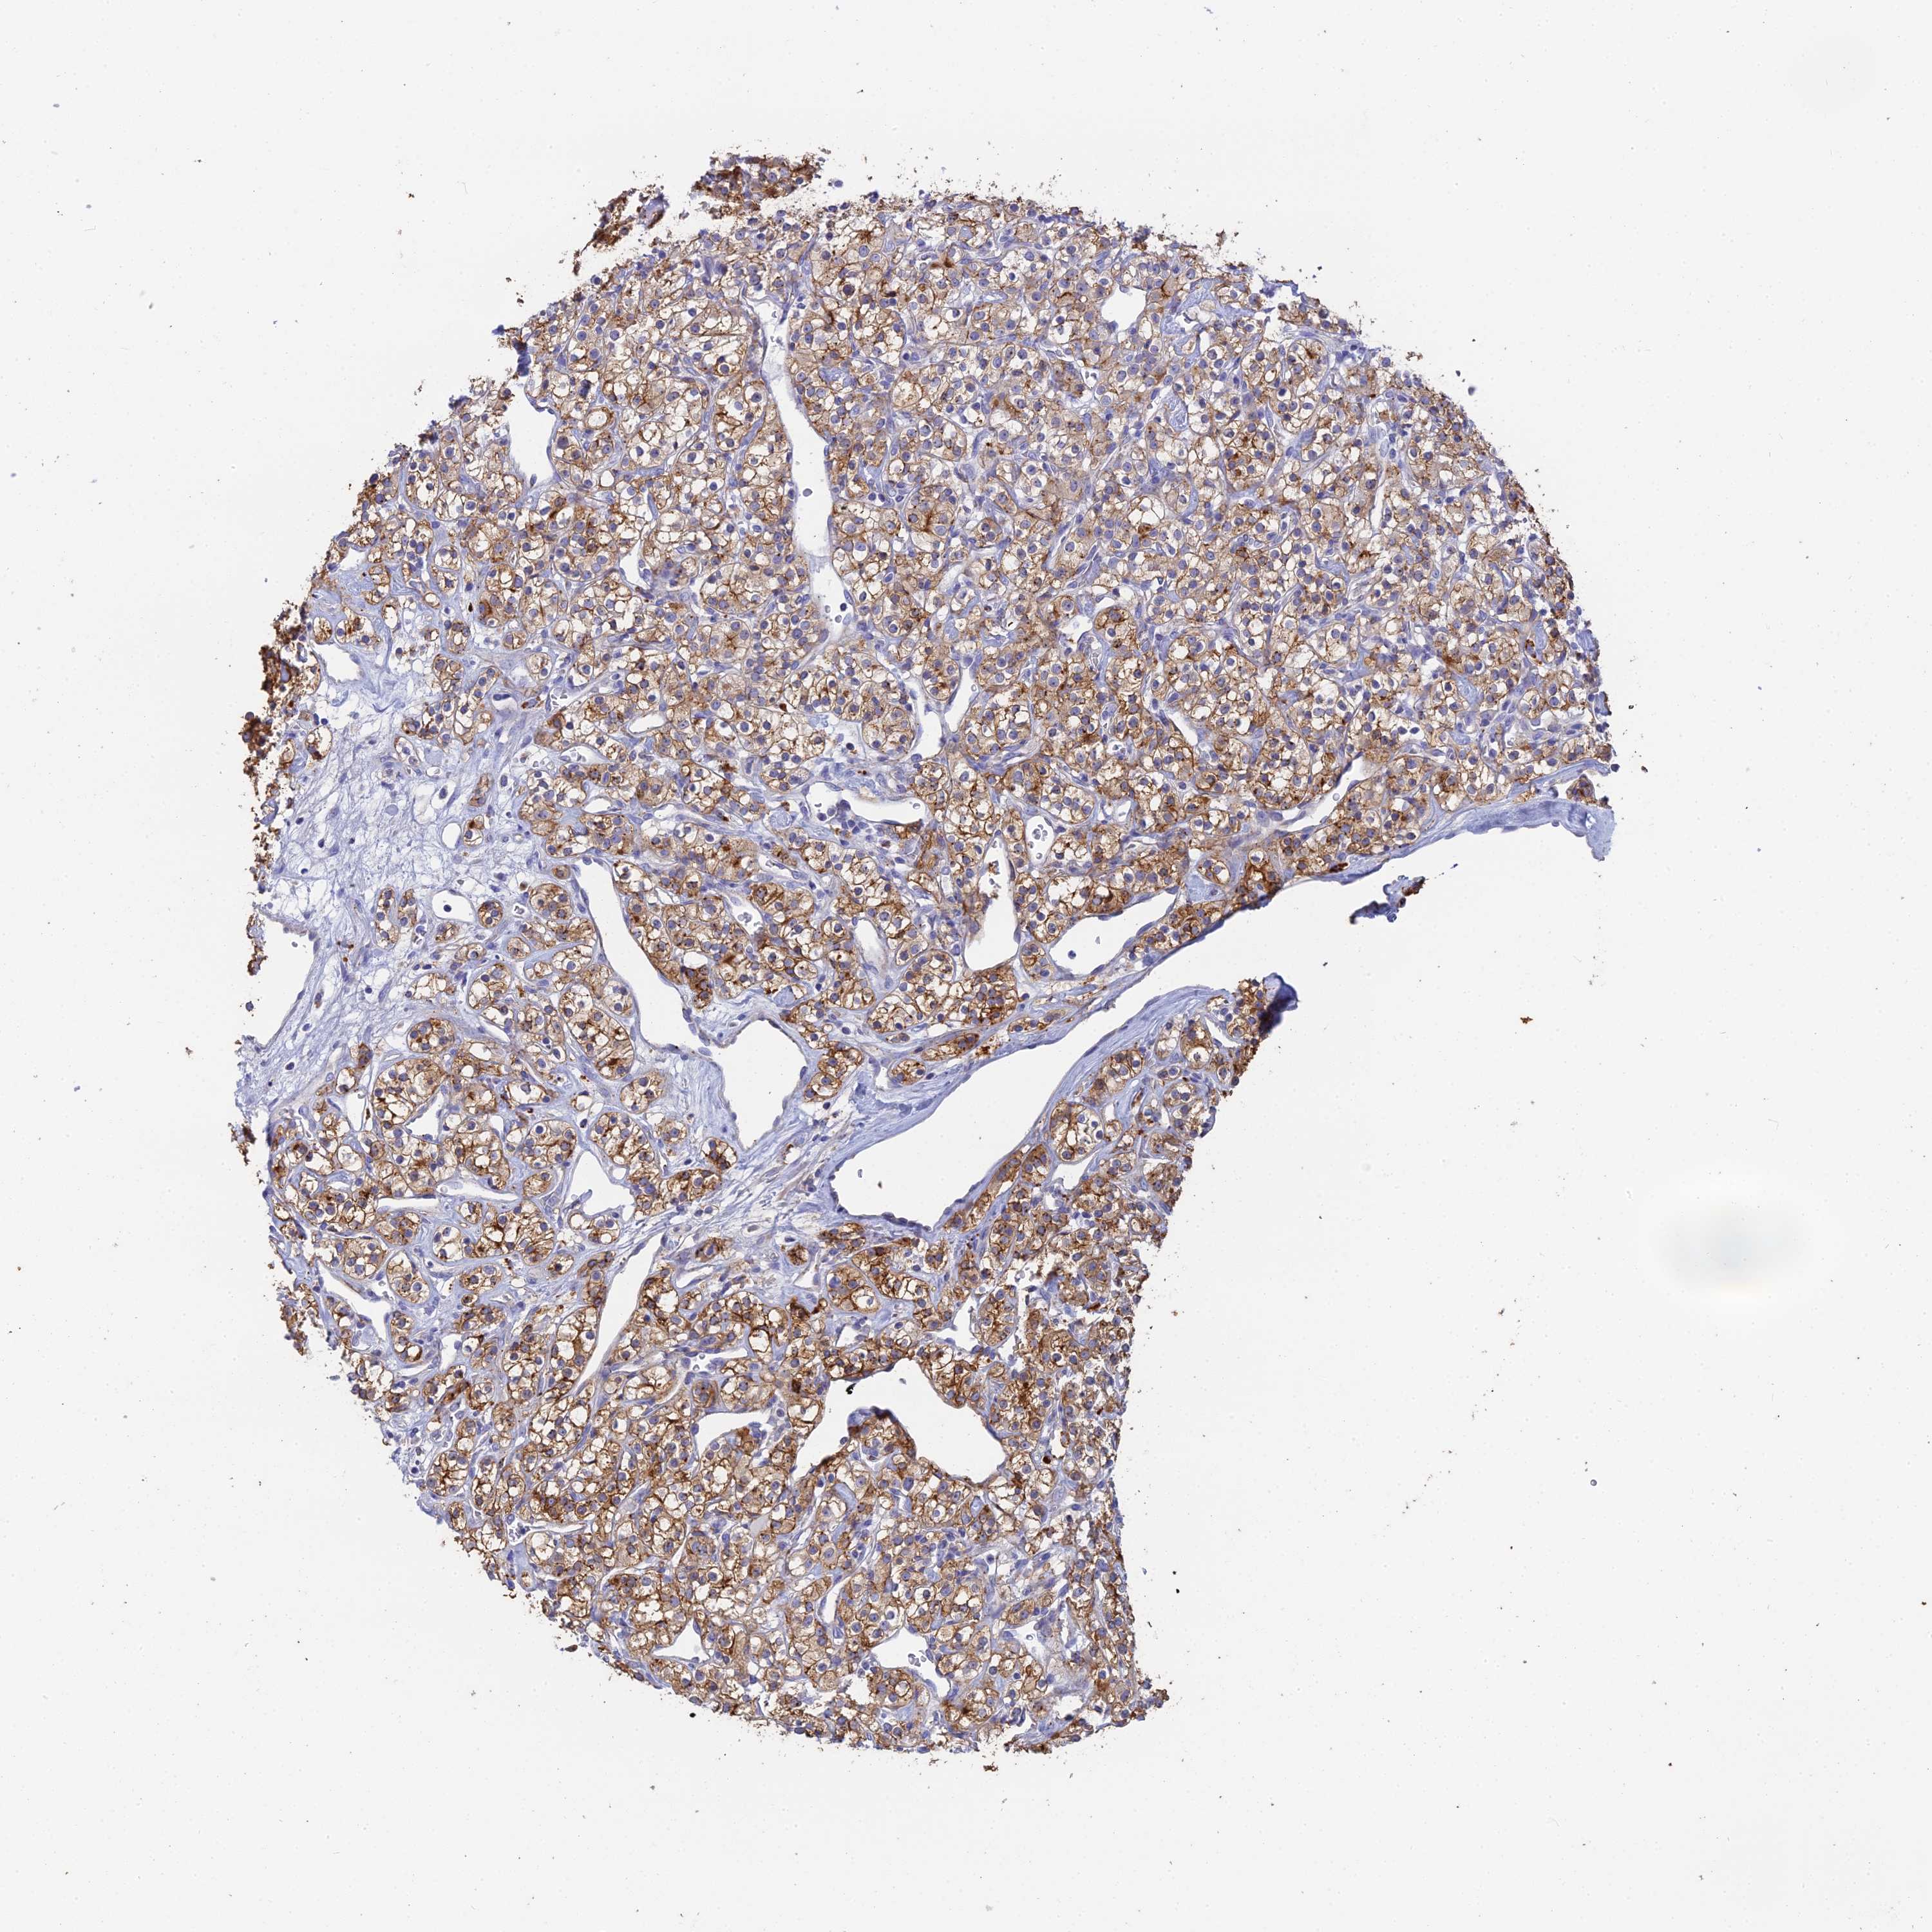

KIDNEY RENAL CLEAR CELL CARCINOMA (TCGA) - Interactive survival scatter ploti

The Survival Scatter plot shows the clinical status (i.e. dead or alive) for all individuals in the patient cohort, based on the same data that underlies the corresponding Kaplan-Meier plots. Patients that are alive at last time for follow-up are shown in blue and patients who have died during the study are shown in red.

The x-axis shows the expression levels (FPKM) of the investigated gene in the tumor tissue at the time of diagnosis. The y-axis shows the follow-up time after diagnosis (years). Both axes are complimented with kernel density curves demonstrating the data density over the axes. The top density plot shows the expression levels (FPKM) distribution among dead (red) and alive patients (blue). The right density plot shows the data density of the survived years of dead patients with high and low expression levels respectively, stratified using the cutoff indicated by the vertical dashed line through the Survival Scatter plot. This cutoff is automatically defined based on the FPKM cutoff that minimizes the p-score. The cutoff can be changed by dragging the vertical line or by entering a cutoff value in the square labeled "Current cut-off".

Under the Survival Scatter plot the p-score landscape (black curve; left axis) is shown together with dead median separation (red curve; right axis). Dead median separation is the difference in median mRNA expression between patients who have died with high and low expression, respectively. It is calculated as follows: median FPKM expression of dead patients with high expression - median FPKM expression of dead patients with low expression. This is intended to aid the user in visually exploring custom cutoffs and the associated p-scores and dead median separation.

Individual patient data is displayed and can be filtered by clicking on one or more of the category buttons on the top of the page. Categories describing expression level and patient information include: high, low, alive, dead, female, male and tumor stages. The scale of the x-axis can be toggled between linear and log-scale by clicking on the "x log" button. Mouse-over function shows TCGA ID, patient information and mRNA expression (FPKM) for each patient.

& Survival analysisi

Kaplan-Meier plots summarize results from analysis of correlation between mRNA expression level and patient survival. Patients were divided based on level of expression into one of the two groups "low" (under cut off) or "high" (over cut off). X-axis shows time for survival (years) and y-axis shows the probability of survival, where 1.0 corresponds to 100 percent.

WDR6 is not prognostic in Kidney Renal Clear Cell Carcinoma (TCGA)

: 52.14

Average pTPM 49.3

Number of samples 521